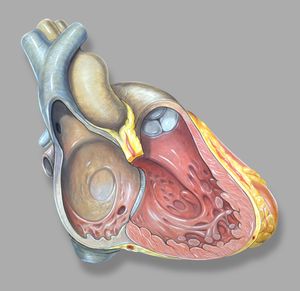

인간의 심장은 우심방, 좌심방, 우심실, 좌심실의 네 개의 방으로 구성되어 있다. 심방은 위쪽에 있는 두 개의 방으로, 혈액을 아래쪽 두 개의 심실로 보낸다.

우심방과 우심실을 합쳐 우심장이라 부르고, 좌심방과 좌심실을 합쳐 좌심장이라고 부른다. 심방에는 입구에 판막이 없기 때문에,[2] 정맥 박동이 정상적으로 나타나며, 경정맥에서 경정맥압으로 확인할 수 있다.[3][4]

내부에는 거친 빗살근과 히스의 결절능선이 있는데, 이는 심방 내부와 우심방의 매끄러운 부분인 ''정맥동''의 경계 역할을 한다. 정맥동은 대정맥과 관상정맥동의 개구부를 둘러싸고 있는 성인의 잔재이다.[5] 각 심방에는 심방 부속지가 붙어 있다.

2. 1. 우심방

우심방은 상대정맥, 하대정맥, 전심장정맥, 최소심장정맥, 관상정맥동에서 산소가 제거된 혈액을 받아 삼첨판을 통해 우심실로 보낸다. 우심실은 이를 다시 폐동맥으로 보내 폐순환을 하도록 한다.2. 1. 1. 우심방 부속지

'''우심방 부속지'''는 우심방의 앞쪽 윗부분에 위치하며, 앞에서 보면 쐐기 모양 또는 삼각형 모양으로 보인다. 기저부는 상대정맥을 둘러싸고 있다.[6] 우심방 부속지는 우심방의 주머니 모양 연장부이며 빗살근의 섬유망으로 덮여 있다. 심방 중격은 우심방과 좌심방을 분리하며, 이는 우심방의 함몰 부위인 난원와로 표시된다. 심방은 탈분극에 의해 칼슘이온이 관여한다.2. 2. 좌심방

좌심방은 좌우 폐정맥에서 산소화된 혈액을 받아 승모판 (좌심실판막)을 통해 좌심실로 보내 대동맥을 거쳐 전신 순환으로 펌프질한다.[7][8]2. 2. 1. 좌심방 부속지